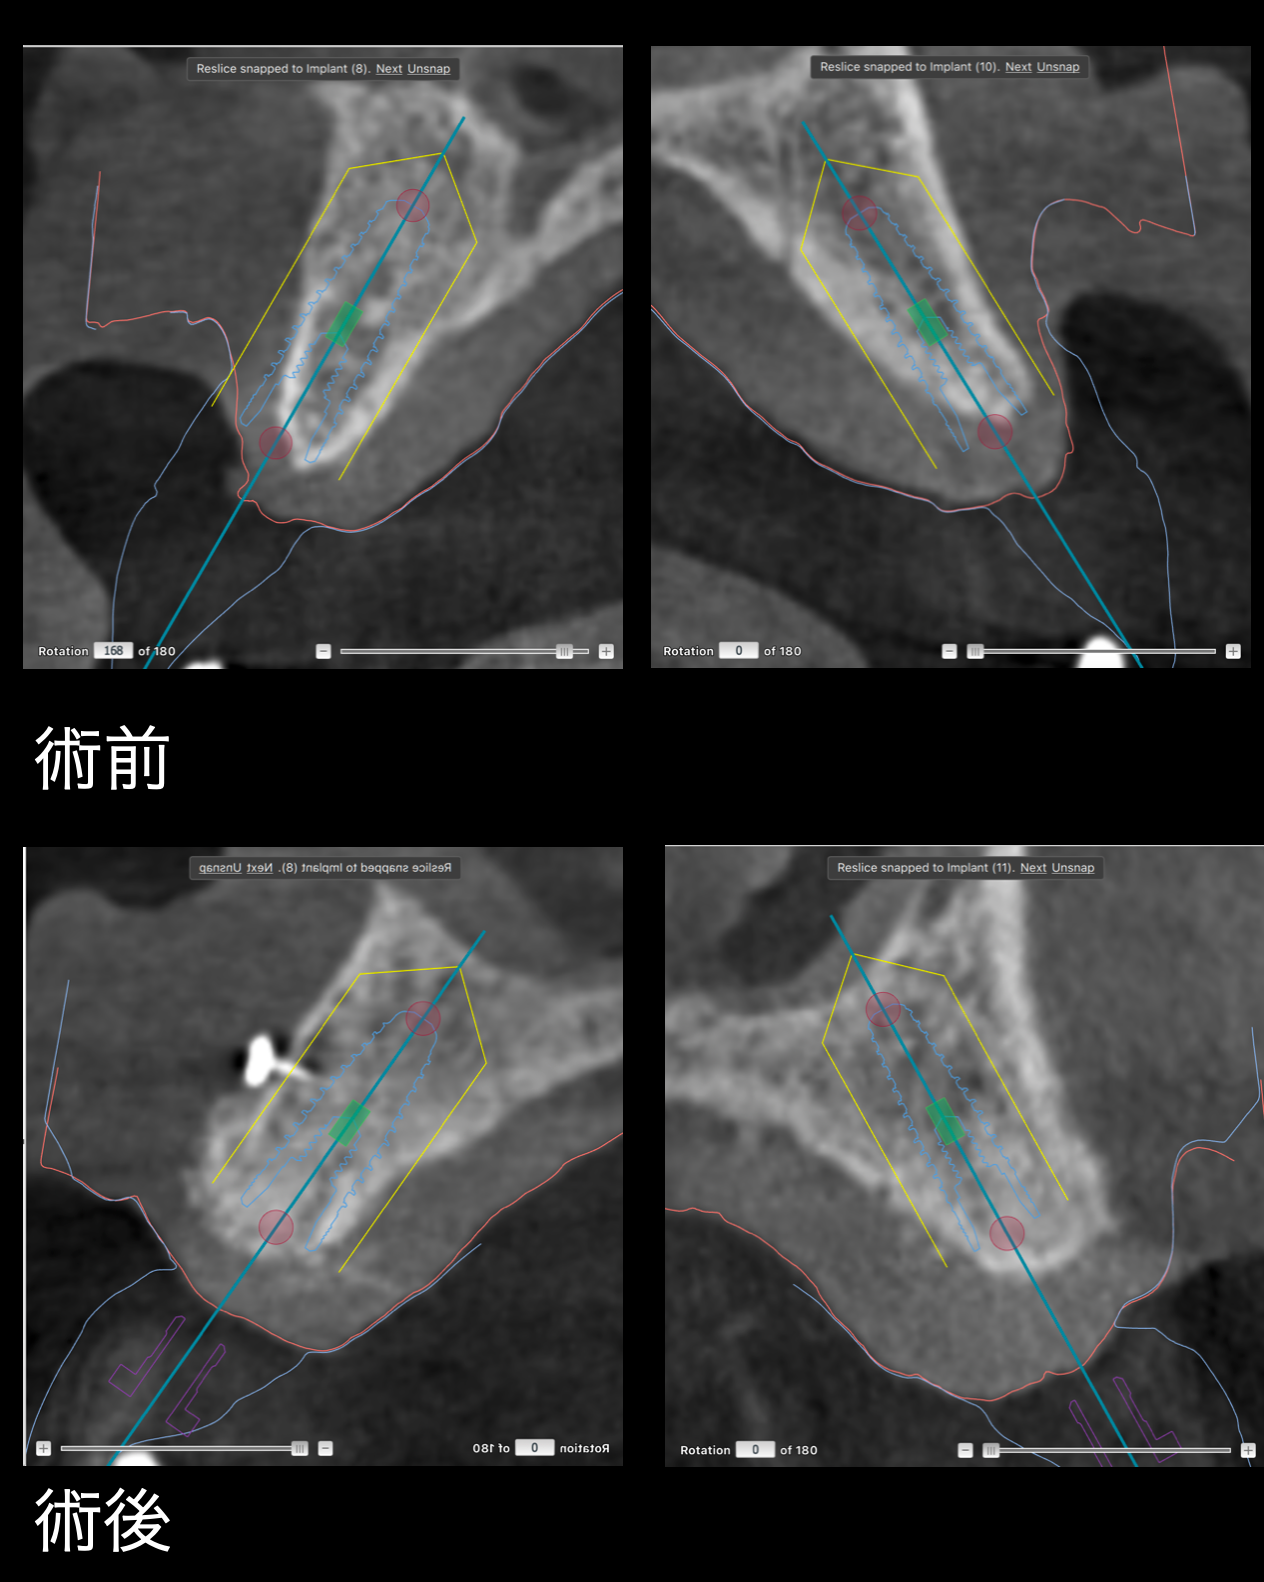

GBRの術前術後のCBCT

術前にはインプラント治療を行うために十分な骨幅がありませんでした。

術後には骨が再生されインプラントを行うだけの十分な幅があります。